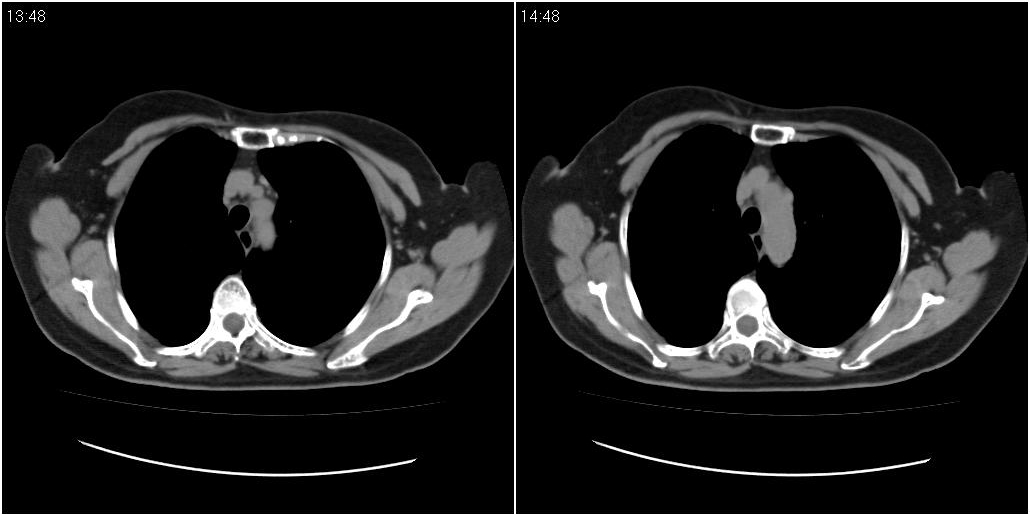

女性,72岁。去年9月份发现肺部病变,诊为肺结核并进行正规治疗至今,但复查后发现ct表现几乎没有变化。

右中间段支气管局限性狭窄,右中叶支气管亦稍显狭窄,但并未见明显占位表现,半年多了,无变化也许是好事,可能为炎性狭窄,建议继续随访。

双肺继发型tb并右中叶内膜tb,轻度支扩,左下胸膜肥厚粘连。

右中叶炎性改变,支气管狭窄但较光滑,占位可能性不大。

右中间段支气管局限性狭窄,右中叶支气管亦稍显狭窄.

双肺继发性肺结核并右肺中叶节段性肺不张,左下胸膜肥厚粘连。

右肺中叶节段性肺不张,考虑结核或慢性炎症,建议做纤支镜检查。